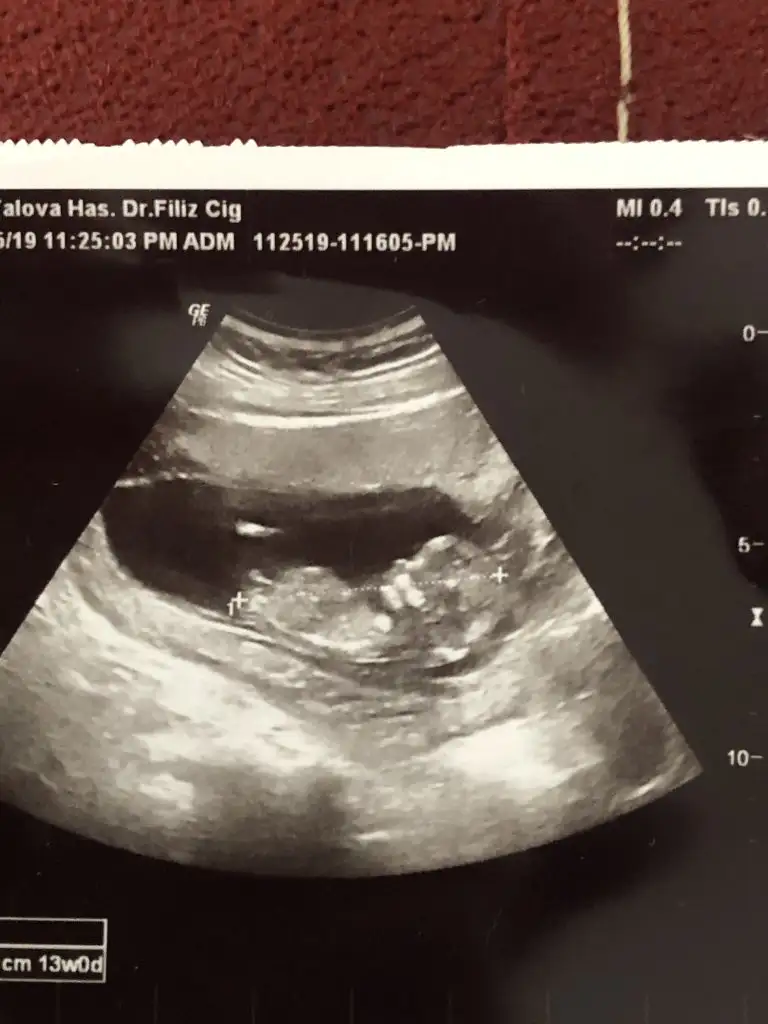

dr soylemeden siz gorun genital nub teorisi ( bebegin cinsiyeti)

Bunlar 12 hafta usg sizce nedir cinsiyet ikra hanımmm çok heycanlıyım doktor bişey söylemedi 😌